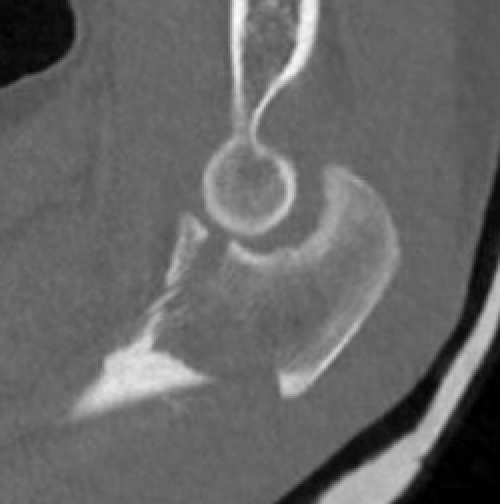

Elbow dislocation + olecranon fracture + radial head/neck fracture +/- coronoid fracture

Complex proximal ulna fracture with radial head replacement subluxation